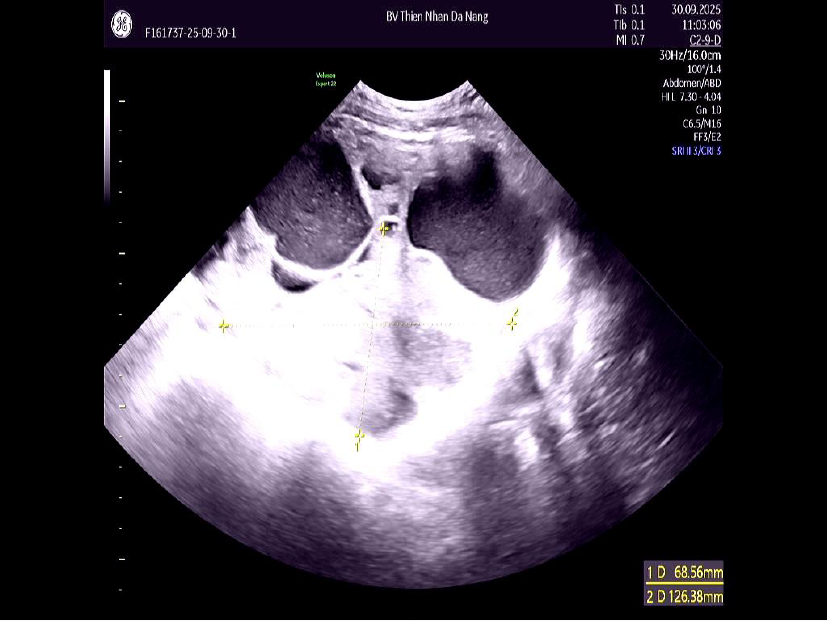

Đến cuối tháng 9/2025, khi xuất hiện đau bụng, chướng vùng rốn và ra huyết âm đạo kéo dài, chị T. đến Thiện Nhân thăm khám. Kết quả siêu âm ghi nhận khối u phát triển nhanh, kích thước 16–17 cm, chiếm gần trọn ổ bụng, tương đương với thai khoảng 6 tháng.

- Kích thước khối u: Buồng trứng trái có khối u 170mm, tăng nhanh so với 140mm chỉ sau 3 tháng.

- Đặc điểm hình ảnh: ORADS 5, mức độ nghi ngờ ác tính rất cao, cao hơn so với kết quả MRI trước đó (ORADS 4).